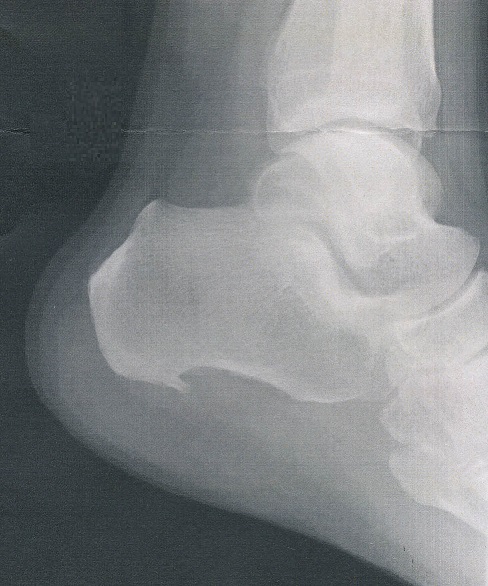

左足のかかとが痛くなっていろいろ診てもらったが変わらず整形外科で診てもらうと『踵骨棘』と診断され、痛み止めを処方された

痛み止めは効かなくてなんでこんなものを処方したのかと思ったが、一緒に処方された湿布でなにか少し変化が感じられる

しかし、痛みは依然変わらない